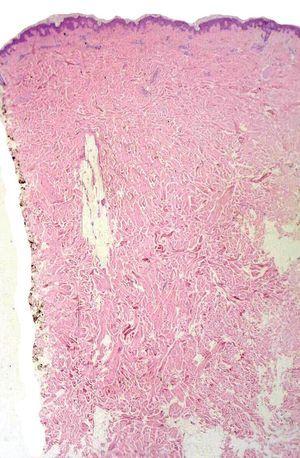

Fig. 2.--El estudio histopatológico mostró un engrosamiento de la dermis reticular con fibras de colágeno ensanchadas y separadas entre sí. (Hematoxilina-eosina, x10.)

Un varón de 64 años de edad con antecedentes de diabetes mellitus tipo 2 complicada con retinopatía, nefropatía, neuropatía y arteriopatía en tratamiento con insulina que consultó por una placa eritematoviolácea empastada al tacto de 2 años de evolución en la parte alta de la espalda, sin repercusión sobre la función respiratoria o la movilidad de tronco o miembros superiores (fig. 1). La bioquímica sanguínea reveló las siguientes alteraciones: glucosa, 269 mg/dl; fosfatasa alcalina, 369 U/l; GOT, 48 U/l; GPT, 94 U/l; GGT, 158 U/l. No se detectaron alteraciones en hemograma, resto de bioquímica y sedimento de orina, hormonas tiroideas, proteinograma, cuantificación de inmunoglobulinas, ANA, anticuerpos antimitocondriales y anti-LKM, serologías para VHB, VHC, VIH, lúes y Borrelia, ni en la radiografía de tórax. Se detectó positividad de los anticuerpos antimúsculo liso (1/80) y la ecografía abdominal mostró hallazgos de esteatosis hepática. El estudio histopatológico mostró fibras de colágeno gruesas separadas por espacios claros en dermis media y profunda sin infiltrado inflamatorio ni incremento de la cantidad de fibroblastos (fig. 2). Las tinciones específicas para mucina mostraron depósitos focales muy discretos. La epidermis e hipodermis eran normales y los anejos cutáneos estaban conservados. La lesión fue tratada con pomada de clobetasol el 0,05 % sin mejoría. El paciente rechazó otros tratamientos. En los últimos meses la lesión se halla estable sin limitar los movimientos del tronco ni alterar la función respiratoria.

Actualmente se usan indistintamente los términos de escleredema o escleredema de Buschke en lugar del de escleredema adultorum ya que muchos pacientes tienen menos de 20 años de edad. En los casos asociados a diabetes los varones se afectan con una frecuencia 10 veces superior a las mujeres. Las lesiones suelen extenderse gradualmente afectando cuello, parte alta de la espalda y hombros y están bien delimitadas 1. Histopatológicamente, el escleredema se caracteriza por un engrosamiento de los haces de colágeno de la dermis reticular separados entre sí por grietas. En ocasiones, puede ser muy difícil demostrar la presencia de mucina, siendo preciso realizar biopsias sucesivas y recurrir a tinciones especiales 2.